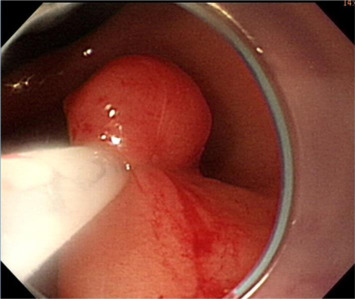

Initially, we administered a submucosal injection of diluted epinephrine along the margin of the larger lesion; however, we were unable to loop the snare around the lesion. A translucent plastic cap (straight distal attachment, MH-462, outer diameter 12.6 mm; Olympus, Tokyo, Japan) was first fixed on the tip of the endoscope and the cap was positioned on the target lesion. Suction was then applied to draw the flat lesion into the cap and, when the suction was released, the flat lesion became a pseudopolyp (Fig. 3 ). Next, we used an electrosurgical snare (oval shape, SD-9L-1, Olympus) to strangle the pseudopolyp immediately before when it became flat (Fig. 4 ). We then resected it with an electrosurgical generator (ERBE VIO 200D, settings with ENDO CUT Q model effect 3, duration 1, interval 5; Elektromedizin, Tübingen, Germany), resulting in an artificial ulcer without active bleeding or perforation (Fig. 5 ). We removed the smaller lesion smoothly by the same method and the total procedure time was 19 minutes. The patient fasted for 1 day and an intravenous proton pump inhibitor was given. Her course after EMR was uneventful and she was discharged 2 days later.

Suction is applied to draw the flat lesion into the cap and, on the release of ...

Figure 3.

Suction is applied to draw the flat lesion into the cap and, on the release of suction, the flat lesion becomes a pseudopolyp.